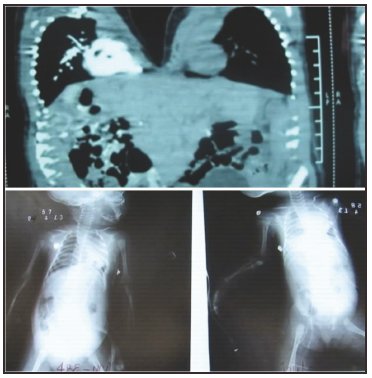

Neonatos Gemelos Monocigóticos Unidos (GMU), de sexo femenino, producto de 37 semanas obtenido por cesárea con peso de 5,620 Kg, APGAR de 7 al minuto y 8 a los 5 minutos. Madre de 24 años con controles prenatales incompletos y padre de 26 años. Ambos con antecedentes de malformaciones colaterales en familiares.

Inmediatamente los GMU ingresaron a cuidados intensivos debido a su condición, al examen físico se observa un puente tisular cutáneo entre las caras anteriores de la región torácica condición que recibe el nombre de GMU TORACOPAGOS, y síndrome de trasfusión leve. Los exámenes complementarios constataron múltiples anomalías: puentes tisulares hepático, pericárdico y vascular en la vena cava inferior, ambas se sometieron a múltiples cirugías con su respectiva separación, de la cual logro sobrevivir una de las siamesas pese a que presentaba comunicación interventricular, una hernia en el abdomen y escoliosis, con su solución, en cambio su gemela falleció por una complicación multifactorial, ya que presentaba el síndrome de Dandy-Walker, Cardiopatías severas y una peritonitis.

Los GMU toracopagos proceden de un solo cigoto que tuvo lugar a una división parcial o a una fusión secundaria de la masa celular interna, línea primitiva o nódulo primitivo entre la primera y segunda semana de desarrollo relacionado con la falta de expresión del gen Goosecoid, ambos son del mismo sexo, tienen características idénticas genotípicas y fenotípicas unidos en mayor proporción por el tórax y en una menor proporción por el abdomen por las que comparten viseras torácicas y abdominales. Se estima que la incidencia de gemelos homocigóticos es de 1 a 2 cada 100.000 nacimientos1,2.